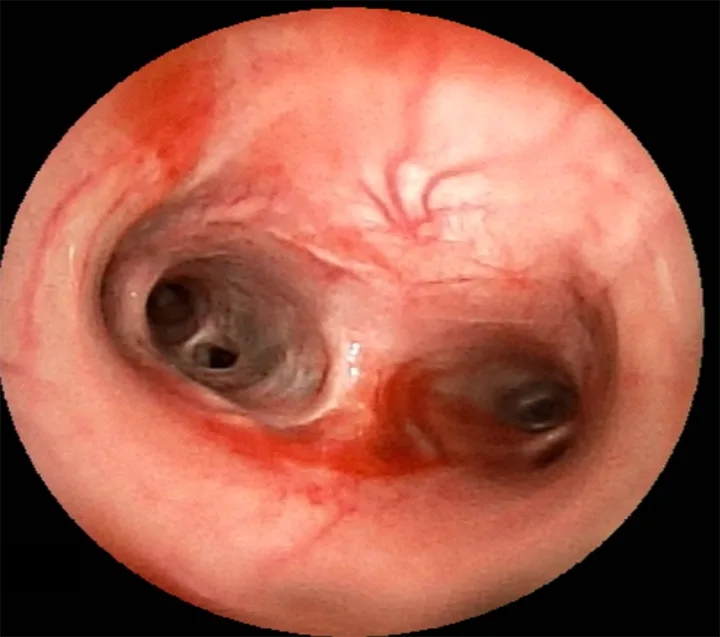

Tracheobronchoscopy

Tracheobronchoscopy can inspect mucosal surfaces of the trachea and lobar bronchi to evaluate mucosal appearance, secretions, and structural abnormalities (Figure 4). This procedure may reveal dynamic airway collapse not identified on thoracic radiography or fluoroscopy; however, anesthesia and inability to cough during the procedure may impact the amount of collapse appreciated.

Tracheobronchoscopy image of carina in a dog.

FIGURE 4

Tracheobronchoscopy image of the carina in an 11-year-old spayed Australian shepherd presented for cough. Mucosa is erythematous, and blood is present at the level of the carina, extending down the left caudal lobar bronchus.